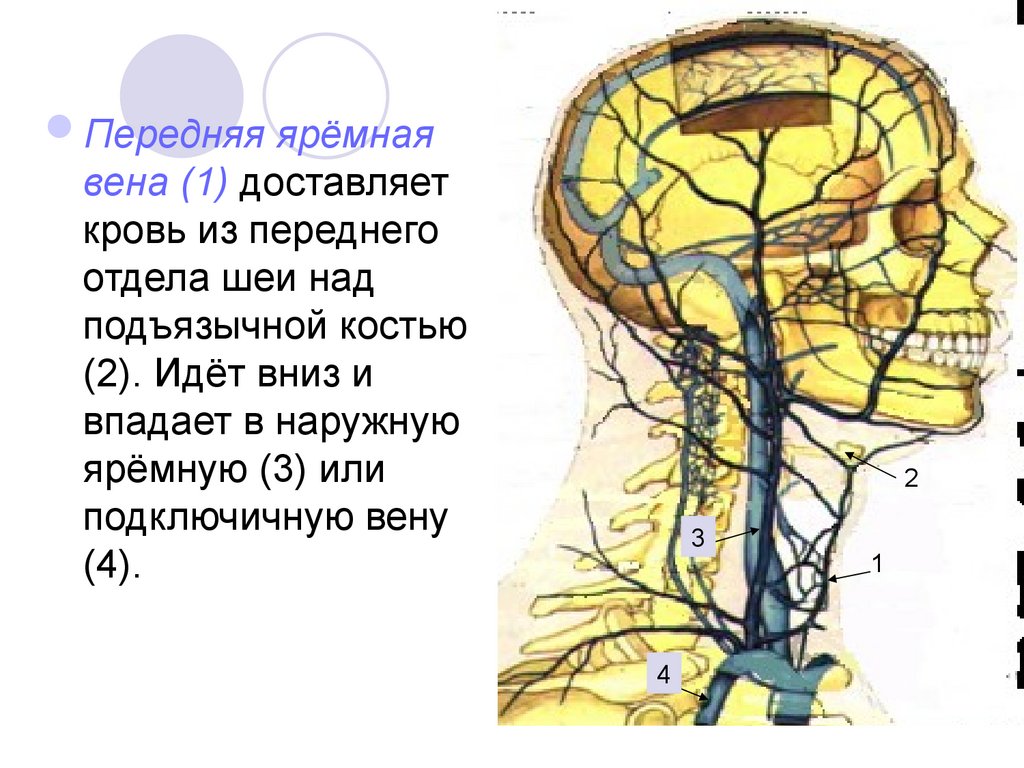

Анатомия внутренней яремной вены: КТ изображения